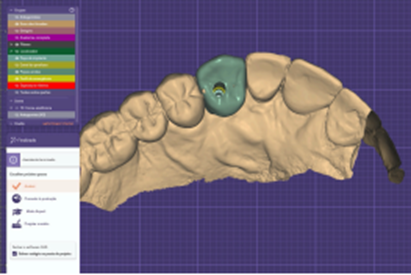

O resultado do escaneamento foi enviado para o laboratório onde foi realizado o projeto e foi feita a fresagem de uma coroa aparafusada em zircônia MultiLayer. A mesma foi maquiada na cor A 3.5 (Figuras 16, 17, 18 e 19).

Figura 16 – Modelo virtual no Exocad

Figura 17 – Projeto do elemento 13

Figura 18 – Projeto pronto para fresagem